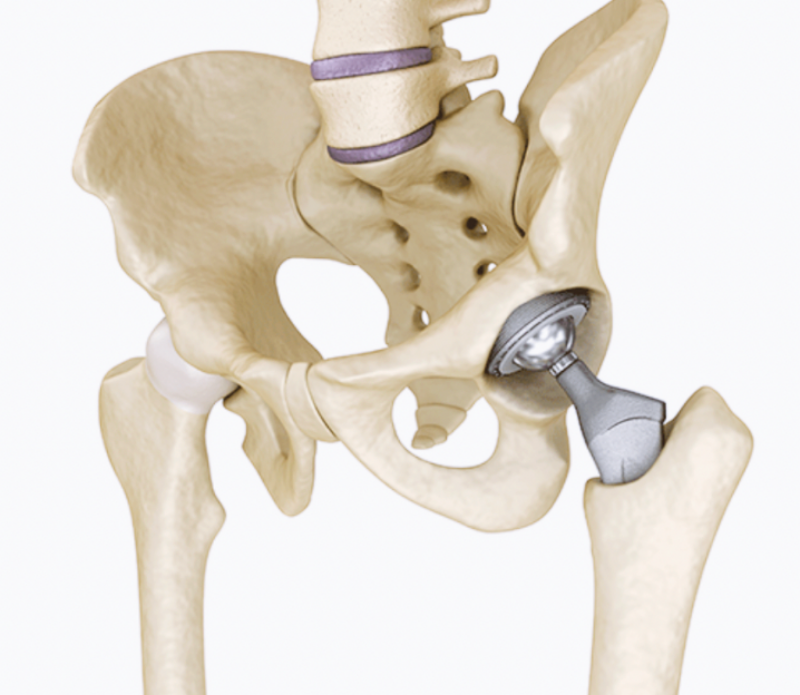

퇴행성 고관절염은 관절 부위의 연골이 닳아 고관절이 관절염으로 인해 손상되는 질환인데요. 우리나라 같은 경우에는 대퇴골두무혈성괴사, 외상 및 골절, 비구이형성증, 선천성 고관절 탈구 등의 후유증으로 발생하는 이차성 퇴행성 고관절염이 흔하게 나타납니다.

7. 대퇴골두 무혈성 괴사

여덟번째 고관절 통증 증상 원인은 대퇴골두 무혈성 괴사입니다. 대퇴골두 무혈성 괴사는 대퇴골두 부분에 혈액순환이 원활하게 되지 않아 뼈가 괴사되는 질병 중 하나인데요. 괴사로 인한 대퇴골두의 손상은 고관절통증과 관절운동의 제한을 만들어내며, 괴사가 진행될 경우에는 고관절 뼈가 붕괴되면서 다리 길이가 짧아지게 됩니다. 이때에는 극심한 고관절통증으로 인해 일상생활이 거의 불가능할 정도입니다.